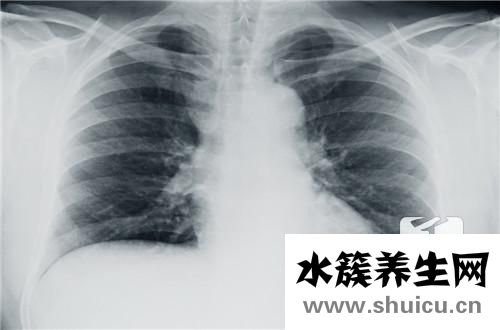

胸痛不是小事,不用覺得過幾天就過去了。如果僅僅是忍受,也許這種情況還會繼續惡化,因為只有疾病才容易引起像人體那樣的疼痛。但是,也有人不信,非要堅持不到醫院。導致原本引起胸痛的病情沒有得到合理...